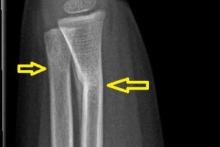

3-latek po urazie przedramienia prawego - kontrola po zdjęciu gipsu

Przypadek 60: 3-latek po złamaniu przynasad dalszych obu kości przedramienia prawego. Badanie kontrolne po zdjęciu gipsu (4 tyg. po urazie).

Rozpoznanie: Na zdjęciach RTG widoczne nawarstwienia okostnowe / odczyny naprawcze w miejscu złamania prawej kości promieniowej, z jej niewielkim kątowym ustawieniem. Niewielkie nawarstwienia okostnowe w okolicy złamania prawej kości łokciowej.